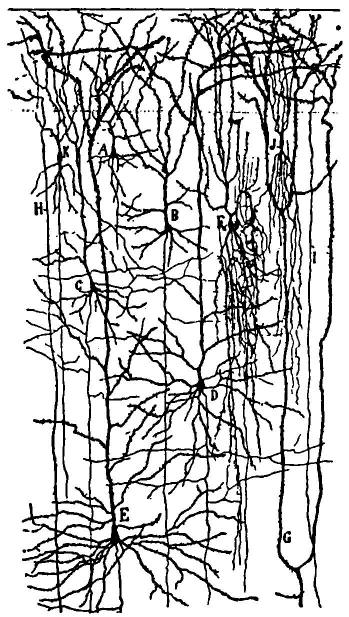

| 2. | Cortex of human brain illustrating complexity of the systems and plexuses of nerve fibers | 109 |

| 20. | Complexity of cell of the central nervous system | 131 |

| 21. | Section through the cortex of the gyrus occipitalis superior | 132 |

| 22. | Motor cell of ventral horn of spinal cord from the human fetus | 133 |